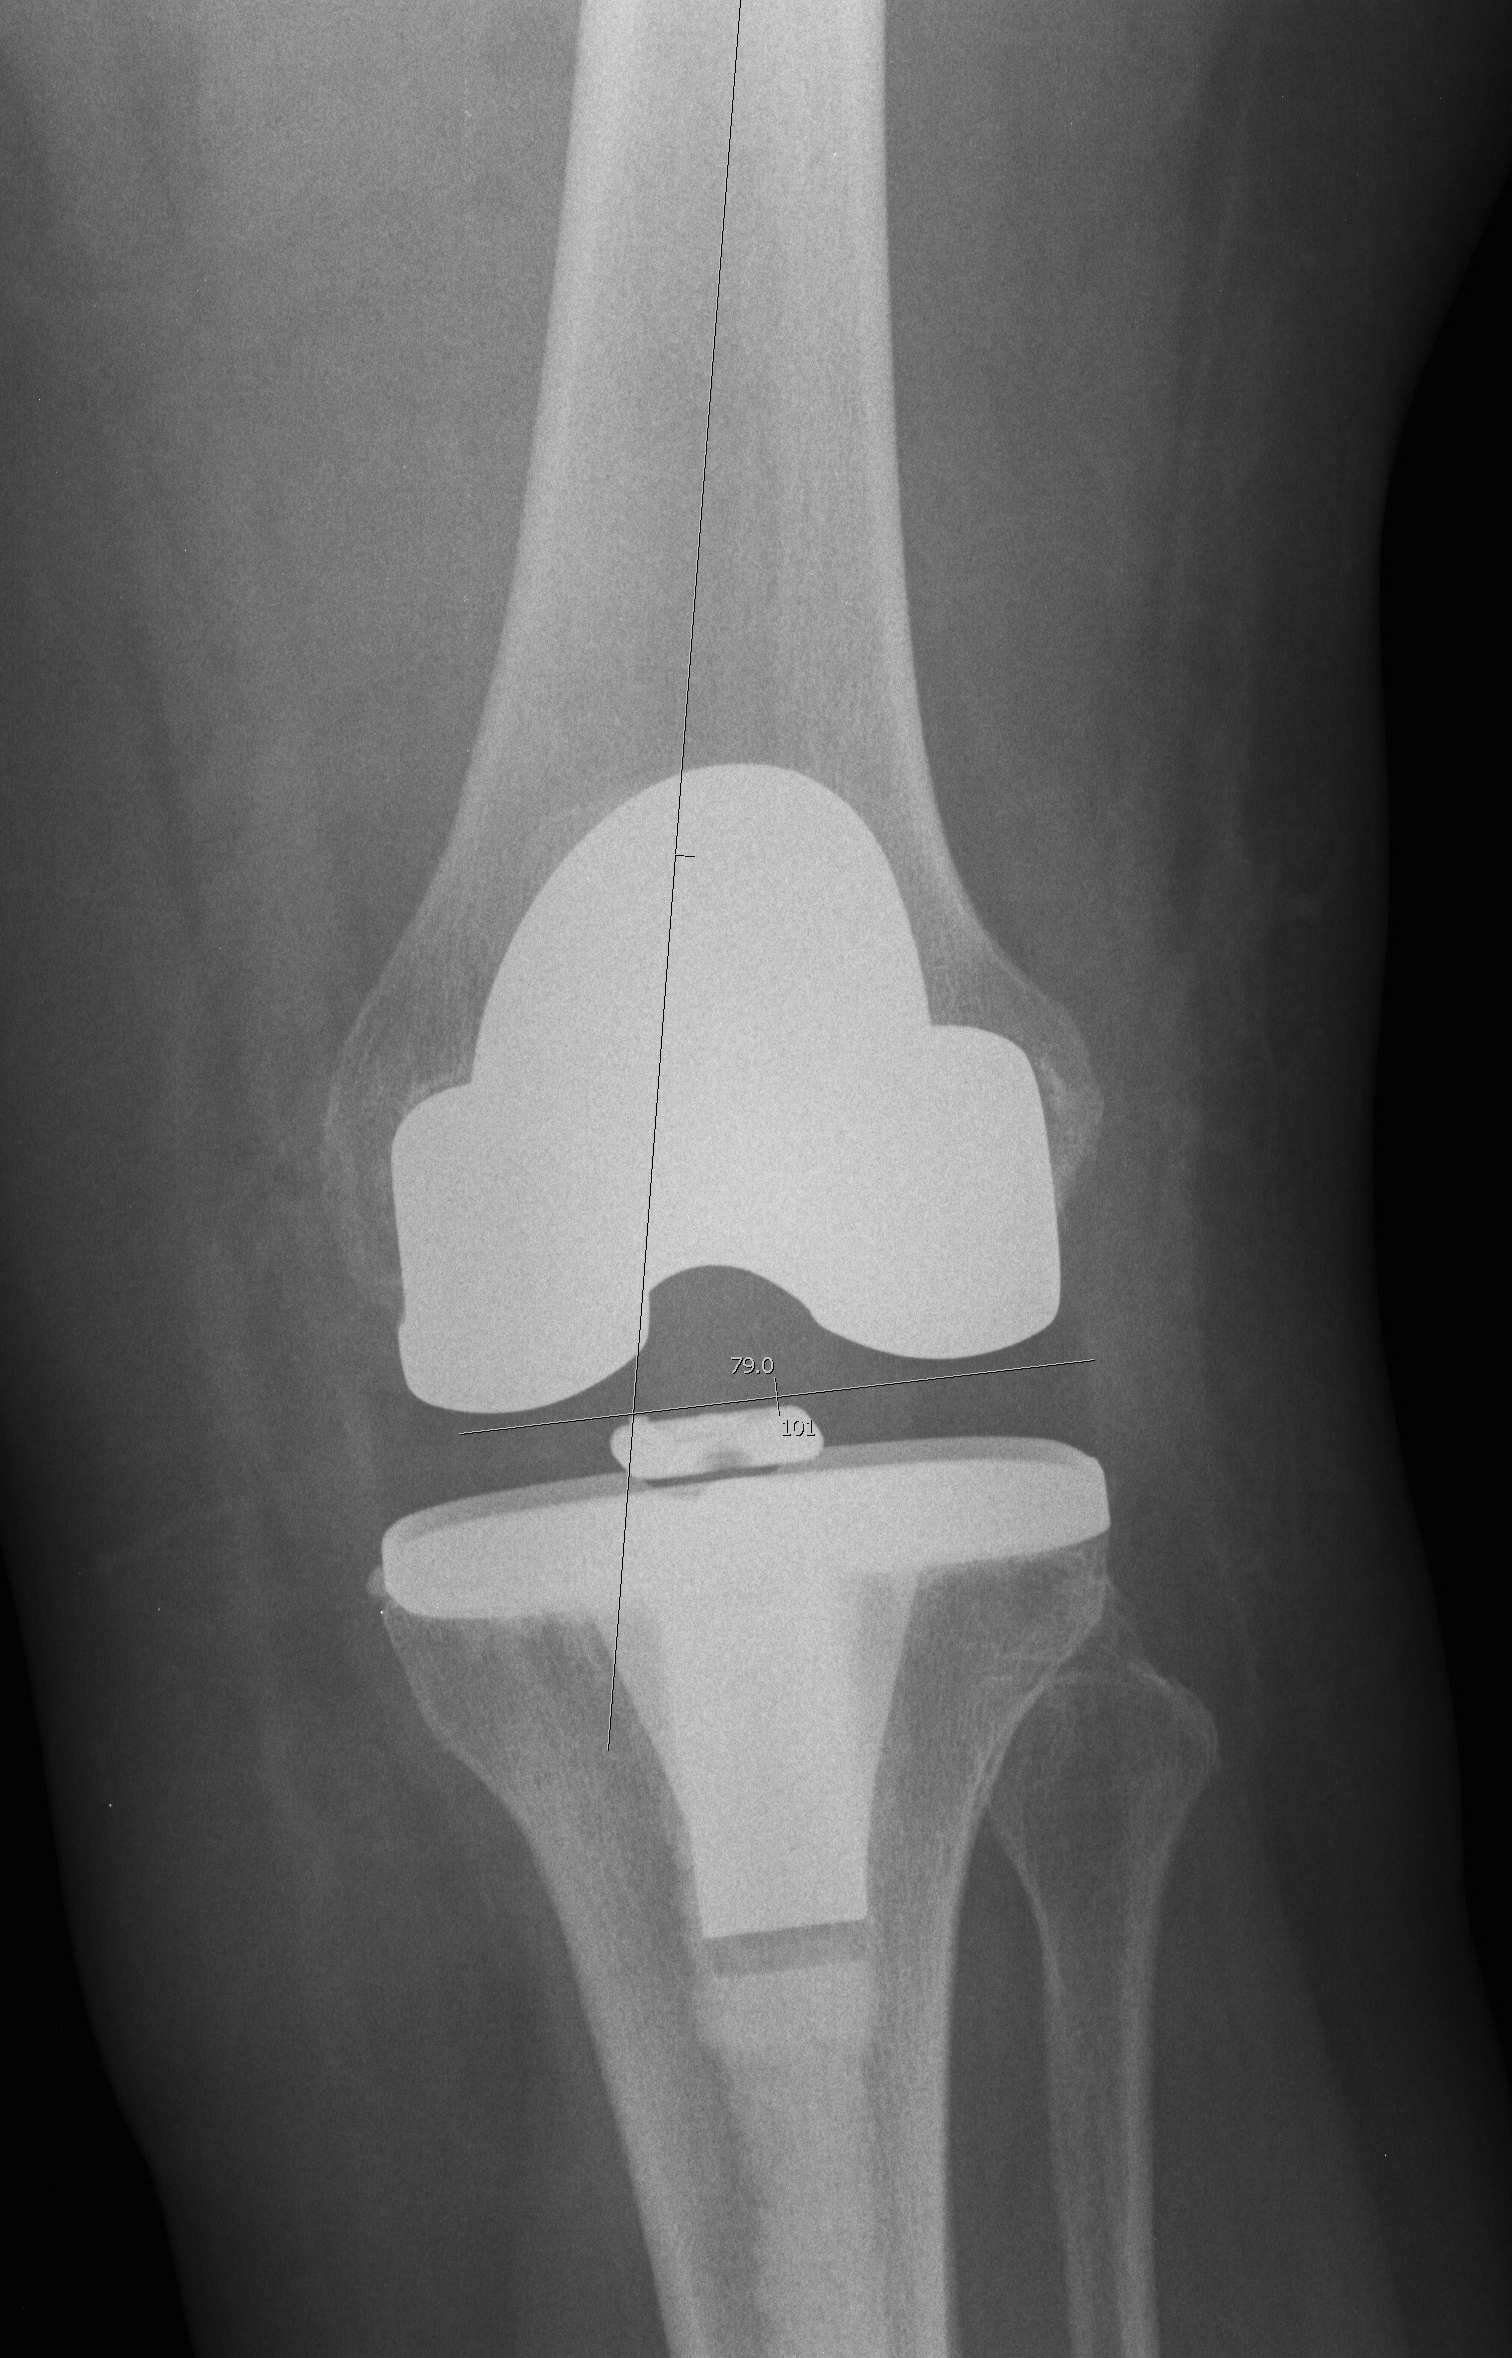

Distal Femoral Resection

Theory

- the tibia is cut at 0o

- want residual tibiofemoral axis to be 3-7o

- therefore, instead of cutting femur at 7-9o valgus, cut at 5-7o

- matched malalignment

Lateral plane

- at right angles to anatomic axis

Alignment

A. Intra-medullary best

B. Extramedullary less accurate

C. Significant deformity of femur / THR

- may need to use EM / short IM / computer navigation

Valgus angle

- pre-op valgus cut angle

- 0o to mechanical axis

- 5 - 7o from anatomical axis

- usually 5o tall and thin, 7o short and fat

Resection depth

- cut 8mm for resurfacing (thickness of femoral component) from most distal surface

- increase if FFD (10 mm)

- sets joint line

- the 8 - 10 mm will always be from the lateral side

- the thickness of the medial resection is > thickness of lateral resection